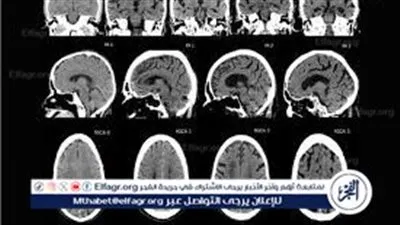

ضمور المخ.. درجات الإصابة به وطرق علاجه

ضمور المخ البسيط عند الأطفال.. تعرف على أعراضه وطرق علاجه

"مرض السكتات".. ما لا تعرفه عن "ضمور المخ" عند الأطفال